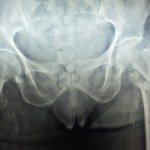

Oncology Case Study and Quiz- 1

Courtesy: James Wittig

Orthopaedic Oncologist

Onco case study and Quiz